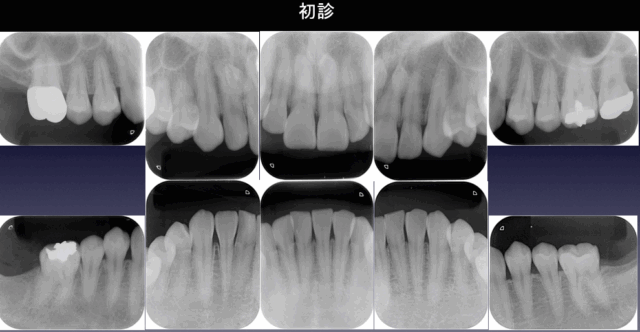

before